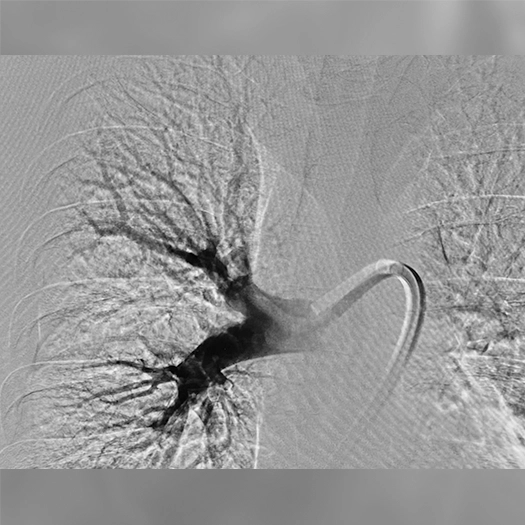

Pulmonary Embolism Cases

Images used with permission and provided for illustrative purposes only. Procedural techniques and decisions based on physician’s medical judgment. Individual results may vary. Consents on file at Penumbra, Inc.